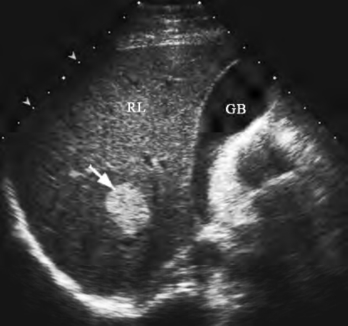

(1)高回声型:为最常见类型,见边界清楚的高回声区,回声分布均匀,呈浮雕样,其间可见呈筛状的小无回声区(图23-20)。

图23-20 肝血管瘤声像图

肝右叶见边界清楚的圆形高回声区